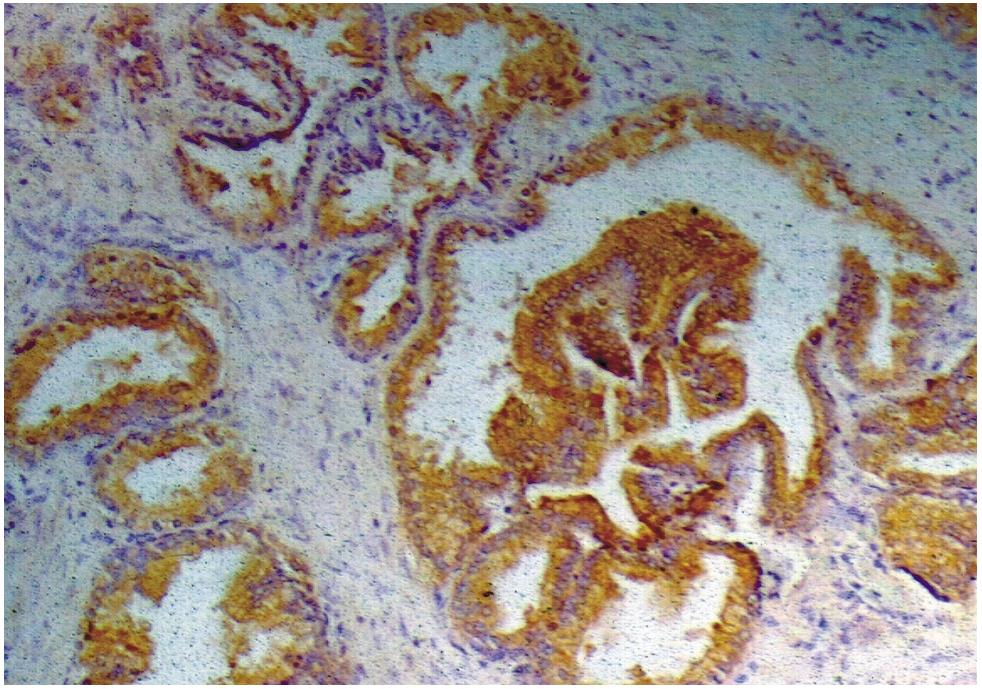

Immunohistochemistry staining of prostate (paraffin-embedded sections) with anti-human Prostate-specific antigen (A67-B/E3).

Immunohistochemistry staining of human prostate (paraffin-embedded sections) with anti-PSA (A67-B/E3), 10 μg/ml. Commercially tested by LifeSpan BioSciences.